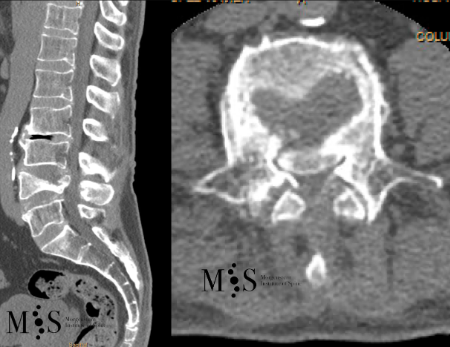

Pre- and post-operative comparison of a cemented kyphoplasty

Female, age 55, compression fracture of L2

Before 1

After 1

Before 2

after 2

Clinical case example of a lumbar vertebral body resection (corpectomy) and reconstruction of a burst fracture at level L4.